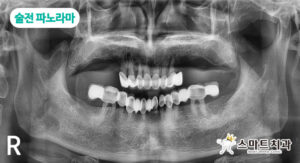

술전 파노라마 사진입니다. 상악은 8개짜리 브릿지와 부분 틀니를 사용 중이시고, 하악은 6개&8개짜리 브릿지 2개를 사용 중인 것을 볼 수 있습니다.

상악 전치부는 전체적으로 골소실이 심하여 전악 발치 후 임플란트 9개 식립과 브릿지 치료 계획을 수립했습니다. 하악은 지대치 9개가 모두 역시 골소실이 심한 상태였기에 환자분과의 충분한 상담을 통해 전악 발치 후 상악과 마찬가지로 임플란트 9개 식립과 브릿지 치료 계획을 수립하였습니다.